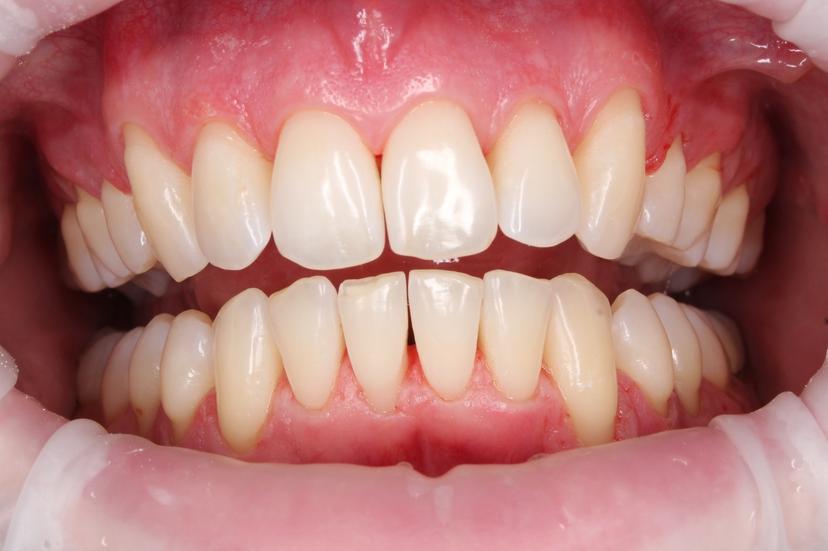

После: Поверхность зубов очищена, восстановлен их естественный цвет, отсутствуют твердые зубные отложения и налет. Зубы выглядят здоровыми и ухоженными, а десны - свежими и более розовыми.